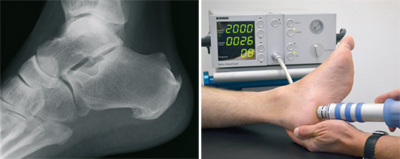

The plantar Calcaneal (at the bottom of the heel) is caused by an overload of the longitudinal arch braced fascia. Connective tissue, excessive loads, malposition, but also overweight may be responsible. The congestion between the heel bone and the attachment site of this fascia is an increasing tissue damage associated with a ossification, called Calcaneal. Not the spur itself, but this tissue damage is causing the pain. They start appearing when putting pressure on it, but later also at rest. First of all the available treatments is the supply of special arch supports. Also injections directly to the Calcaneal, have their value. The shock wave therapy as proved to be very risk-free, which is carried out in our practice. Alternatively, X-ray irradiation effect healing.

Failure of all non-operating activities is also a surgical treatment option. Via a small cut at the inner edge of the heel fascia is nicked, the voltage decreases and the tissue damage can heal.